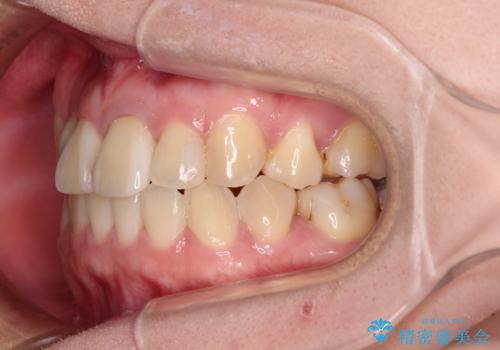

- 奥歯が痛いとのことで来院された患者様です。

上顎親知らず周辺の炎症と、神経組織の失活した歯の炎症による痛みが認められたため、親知らずの抜歯と根管治療を行いました。

根管治療を行った歯はクラウンによる補綴治療が必要となりますが、高校生の頃に行った矯正治療の後戻りも気になるとのことで、補綴治療を行う前に矯正治療を行うこととしました。

後戻りは軽度であり、インビザラインにて歯列を整え、その後にオールセラミッククラウンにて補綴治療を行うこととしました。